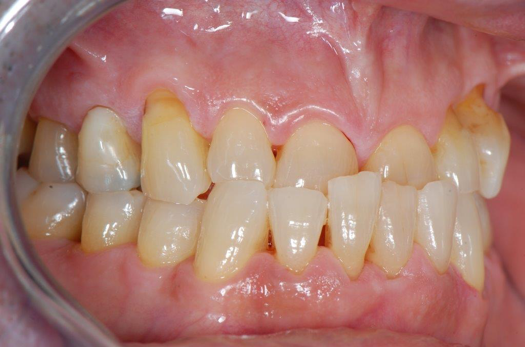

Fig 26. Titanium versus ceramic.

Figure 26

Figure 26 allows a visual inspection and comparison of the soft-tissue profiles of a two-piece titanium implant and neighboring one-piece ceramic implant. The image suggests that the ceramic material not only has a better attachment of soft tissue, but a better cosmetic component. The restoring and surgical dentists should consider thin soft-tissue profiles of the patient when deciding on the implant material of choice.